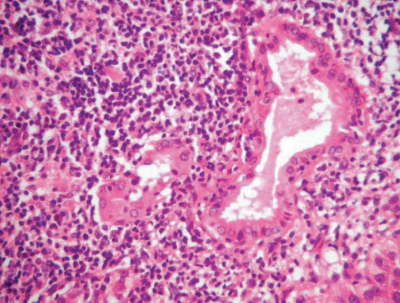

血液所見:赤血球496万、Hb 14.8 g/dL、Ht 44%、白血球 5,200、血小板 25万。血液生化学所見:総蛋白 7.5 g/dL、アルブミン 3.9 g/dL、AST 26 U/L、ALT 32 U/L、ALP 238 U/L(基準 38~113)、γ-GT 266 U/L(基準 8~50)。免疫血清学所見:HBs抗原陰性、HCV抗体陰性。肝生検組織の門脈域のH-E染色標本を別に示す。